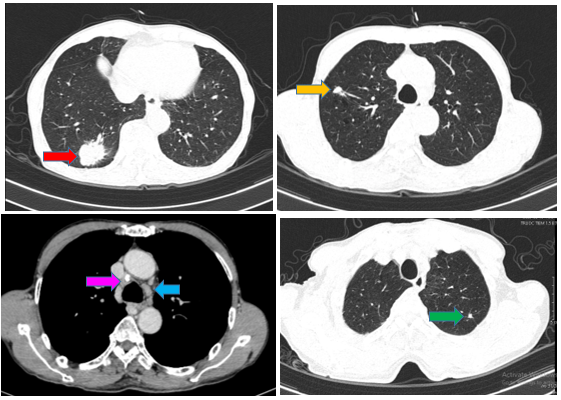

- Chụp cộng hưởng từ sọ não tháng 10/2024 (trước điều trị)

Hình 2:

Vỏ não thùy trán hai bên và thùy đỉnh phải có các nốt tăng ngấm thuốc sau tiêm, nốt lớn nhất ~ 4mm (mũi tên đỏ) – Theo dõi thứ phát

+ Chụp MRI sọ não sau điều trị:

Hình 8: So sánh phi chụp cộng hưởng từ sọ não trước điều trị có nốt tăng ngấm thuốc sau tiêm vùng vỏ não thùy trán thùy đỉnh phải ~ 3mm (mũi tên đỏ) của phim chụp trước điều trị. Hiện tại chụp lại phim MRI não đã không còn phát hiện các nốt ngấm thuốc bất thường.